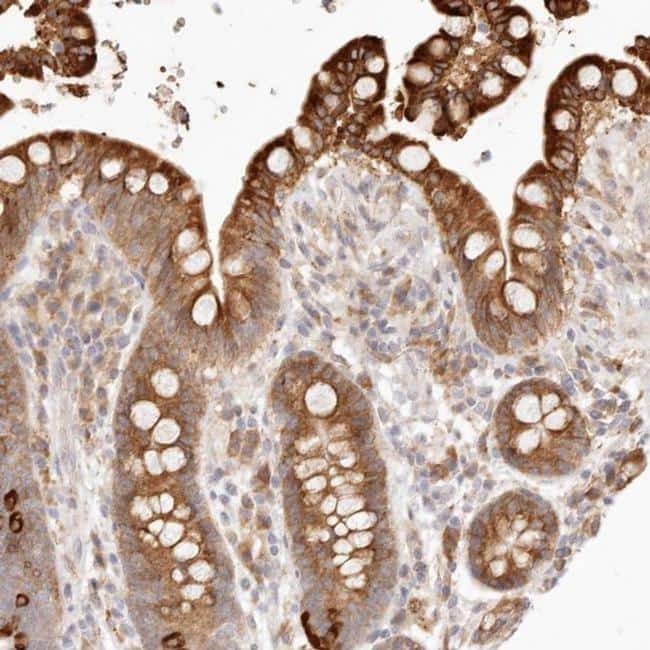

Supportive validation

- Submitted by

- Invitrogen Antibodies (provider)

- Main image

- Experimental details

- Immunohistochemical analysis of C1orf127 in human colon using C1orf127 Polyclonal Antibody (Product # PA5-55672) shows strong cytoplasmic positivity in glandular cells.